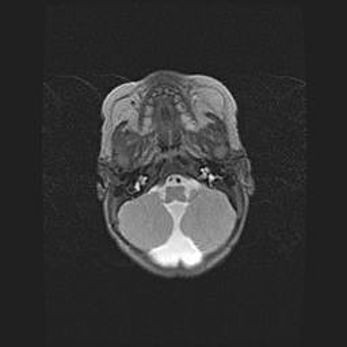

Церебральная ишемия II.

Возраст: 5 дней

Вес: 3400 г

Пол: женский

Окружность головы: 35 см

Срок гестации: 39 недель

Церебральная ишемия – это заболевание, характеризующееся недостаточностью (гипоксией) либо полным прекращением (аноксией) снабжения мозга кислородом по причине закупорки одного или нескольких сосудов. Это приводит к  что метаболическим расстройствам различной степени тяжести в тканях головного мозга, развитию коагуляционных некрозов и гибели нейронов.